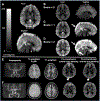

Persons with sickle cell disease (SCD) suffer from chronic hemolytic anemia, reduced blood oxygen content, and lifelong risk of silent and overt stroke. Major conventional stroke risk factors are absent in most individuals with SCD, yet nearly 50% have evidence of brain infarcts by the age of 30 years, indicating alternative etiologies for ischemia. We investigated whether radiological evidence of accelerated blood water transit through capillaries, visible on arterial spin labeling (ASL) magnetic resonance imaging, reduces following transfusion-induced increases in hemoglobin and relates to oxygen extraction fraction (OEF). Neurological evaluation along with anatomical and hemodynamic imaging with cerebral blood flow (CBF)-weighted pseudocontinuous ASL and OEF imaging with T2 -relaxation-under-spin-tagging were applied in sequence before and after blood transfusion therapy (n = 32) and in a comparator cohort of nontransfused SCD participants on hydroxyurea therapy scanned at two time points to assess stability without interim intervention (n = 13). OEF was calculated separately using models derived from human hemoglobin-F, hemoglobin-A, and hemoglobin-S. Gray matter CBF and dural sinus signal, indicative of rapid blood transit, were evaluated at each time point and compared with OEF using paired statistical tests (significance: two-sided p < 0.05). No significant change in sinus signal was observed in nontransfused participants (p = 0.650), but a reduction was observed in transfused participants (p = 0.034), consistent with slower red cell transit following transfusion. The dural sinus signal intensity was inversely associated with OEF pretransfusion (p = 0.011), but not posttransfusion. Study findings suggest that transfusion-induced increases in total hemoglobin may lengthen blood transit times through cerebral capillaries and alter cerebral OEF in SCD.